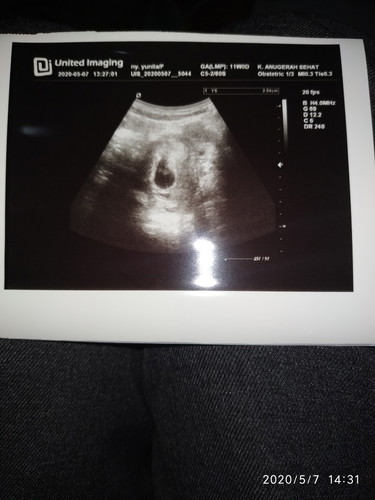

Hamil 7weeks tapi kantung belum terlihat

Bunda mau nanya dong ada gak ya disini yg hamil 7minggu tapi belum keliatan kantung sama janinnya? Ini kehamilan ke 3 aku setelah keguguran 2x , kamarin aku telat 1minggu aku tespek positif terus aku periksa ke bidan umur kehamilan baru 6weeks dan masih penebalan dinding rahim setelah 1minggu dri bidan kematin aku keluar flek keputihan warna coklat gitu selama 2 hari akhirnya aku memutuskan periksa ke dokter kandungan, pas diperiksa ternyata kantungnya masih belum terlihat bun, dan di sana aku di tespek lagi karna dokter gapercaya kalo tespek ku garis 2, itu kira2 normal ga bun? Akutakut banget soalnya😭 #seriusnanya #bantusharing #ingintahu #pleasehelp